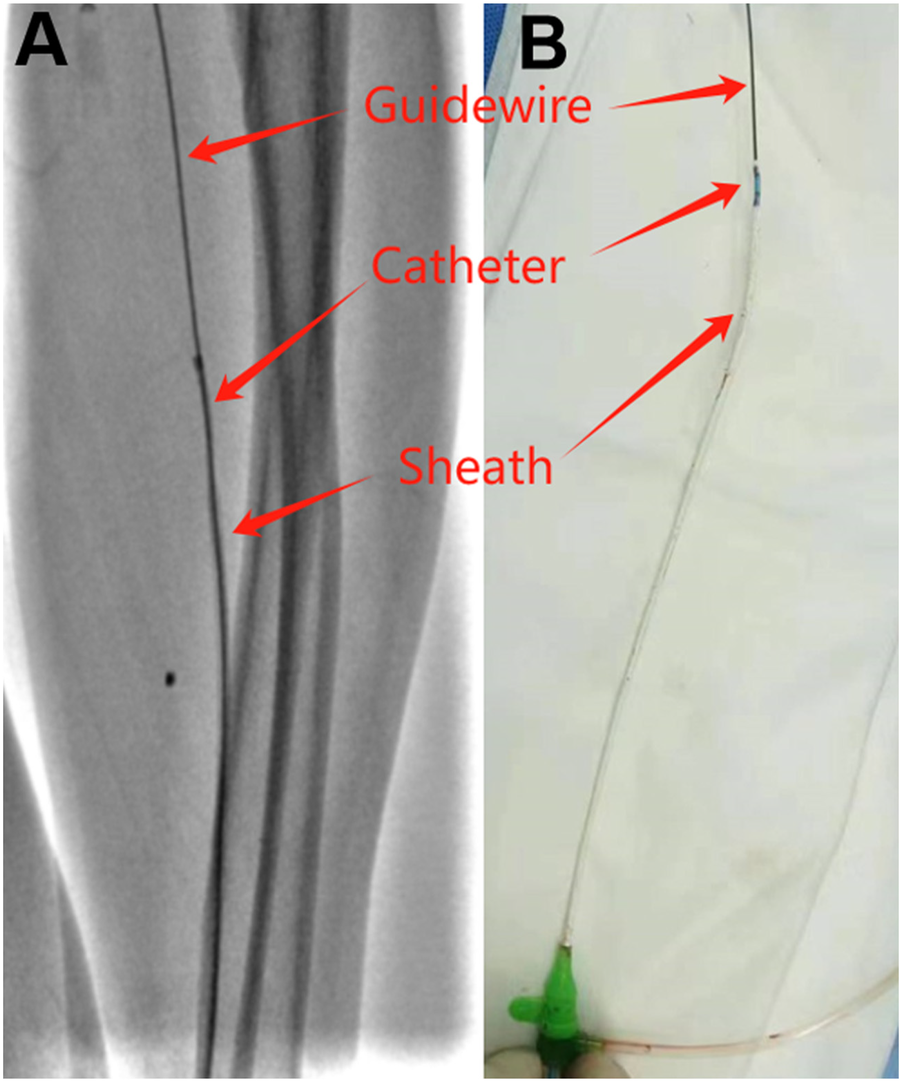

The second patient is a 57-year-old male with a history of myocardial infarction and coronary stent implantation via his right radial artery. He was recently admitted to the hospital due to recurrent chest pain following physical activity. Due to occlusion of the right radial artery, it was decided to perform coronary angiography via the left radial artery. After successful puncture, a 6F Terumo radial artery sheath was inserted, and 3,000 units of heparin along with 100 µg of nitroglycerin were administered through the sheath. Coronary angiography was subsequently completed using 5F JL3.5 and JR 3.5 catheters, revealing occlusion of the posterior descending artery (PDA). A stent was successfully implanted in the RCA-PDA, and the procedure proceeded smoothly, with no reported severe discomfort during the operation. However, upon removal of the 6F Terumo radial artery sheath at the conclusion of the operation, the radial artery experienced spasm, complicating the removal process and resulting in deformation of the sheath. When the sheath deformed, we promptly halted the operation and administered nitroglycerin through the sheath. We then attempted to advance Terumo's own puncture guidewire (0.021 inch), but this was unsuccessful due to the guidewire's excessive softness. Subsequently, we employed a 0.035-inch J-tipped guidewire, which allowed us to successfully advance the guidewire into the brachial artery. With the guidewire's support, we were able to maneuver the 5F JR3.5 catheter into the sheath, achieving integration of the guidewire, contrast catheter, and sheath (Figure 2). Finally, with the assistance of the guidewire and catheter, we carefully and successfully removed the deformed sheath. Post-operatively, the patient reported no significant forearm pain, and the radial artery remained patent both immediately after the procedure and the following day.

Figure 2

Deformed sheath removal with guidewire and catheter assistance. (A) Guidewire, catheter and sheath under fluoroscopy. (B) Guidewire, catheter and sheath in vitro.